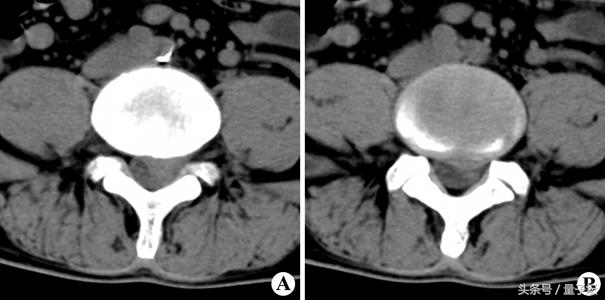

二、CT:近年来,CT检查椎间盘突出症逐渐普及,可显示椎间盘突出的部位、大小、形态和神经根、硬脊膜囊受压移位的情况,还可显示椎板及黄韧带肥厚、小关节增生肥大、椎管及侧隐窝狭窄等情况。在CT图像上椎间盘突出表现为硬膜外脂肪组织消失,椎间盘向椎管内呈丘状突起,若突出钙化,则可显示异常钙化影以及神经根鞘和硬膜囊受突出物挤压移位等情况。对于诊断特殊类型的椎间盘突出,如椎问孑L部突出或极外侧突出,有特别重要的价值。I临床上根据详细病史、体征及普通x线片,在大多数患者可以作出确诊和定位。应强凋CT检查必须结合临床进行判断,才能提高诊断的准确性,完全依靠单纯CT检查并不可靠。

CT检查椎间盘突出症